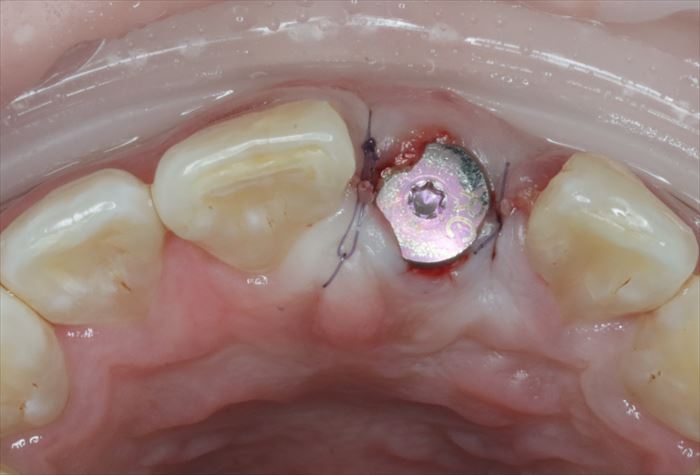

インプラントの埋入を終えました。青いパーツはインプラント埋入用のパーツです。

ゆるくならないようにドリリングの見極めが重要です。

インプラントの埋入深度は、想定する歯頚部よりも最低4㎜深い部分にインプラントネックを位置づけます。

前歯のインプラント埋入位置は口蓋側寄りにすることが審美的要件の大原則です。

インプラント本体の接続部の保護と、歯肉の形態を作るためのヒーリングキャップを準備します。

抜歯後の穴(=抜歯窩:ばっしか)とインプラントとの隙間にハイドロキシアパタイトを填入して骨吸収を防止します。

ヒーリングキャップの締結とハイドロキシアパタイトの填入を終えました。